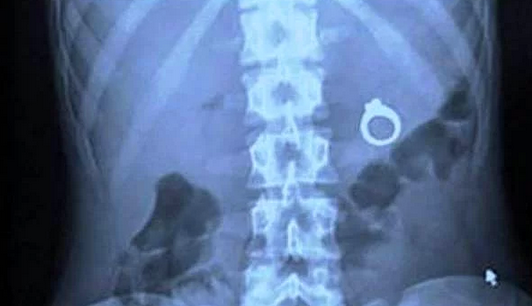

Sürpriz evlenme teklifi

Amerikalı bir adam, sevgilisine sürpriz yapmak için aldığı tektaş yüzüğü kızın milkshakeinin içine koyuyor.. Bu da sonucu